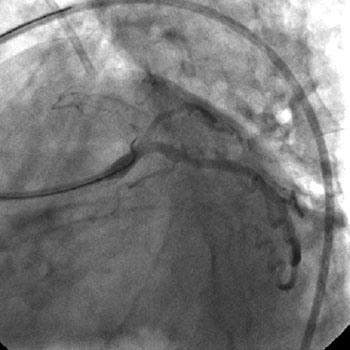

3) LAD: Ostial CTO ( Figure 2) with collaterals from RCA and LCX (Figure 3).